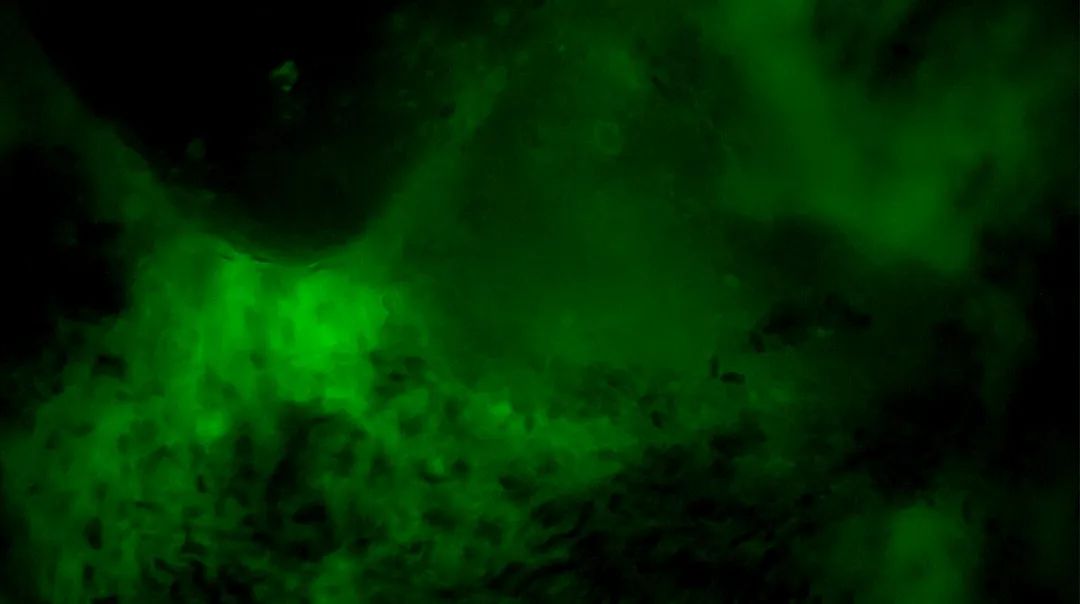

3

陰性,細(xì)胞核形態(tài)正常、分布均勻